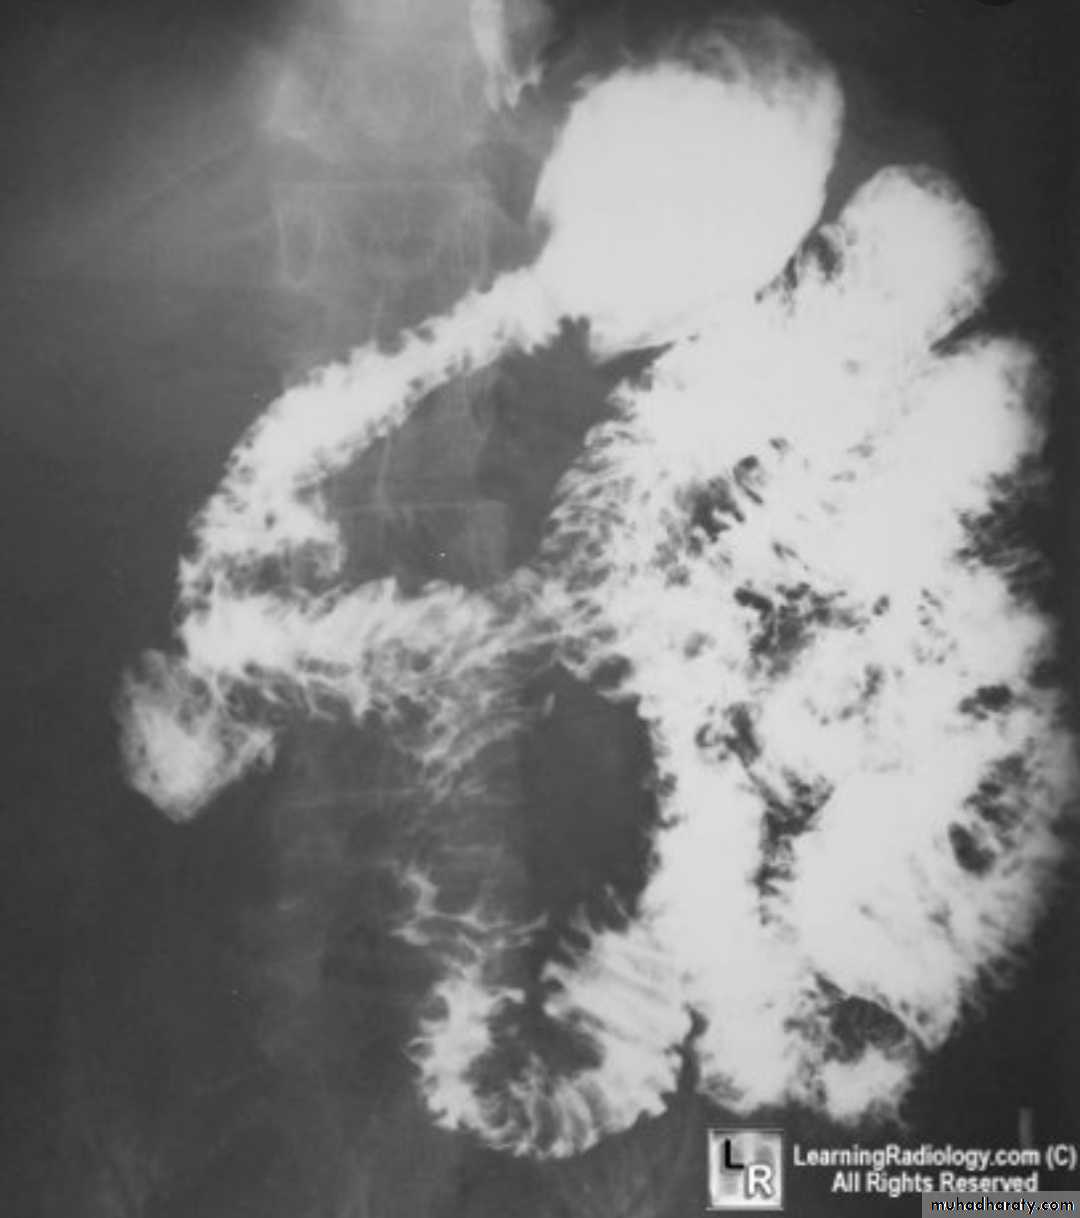

Barium enema 3 presentation

1. infiltrative ( Apple core sign ) lesion infiltrate bowel wall from outside

2.ill defined filling defect within the lumen of the bowel

3.could be ulcerative nodule or ulcerative lesion .